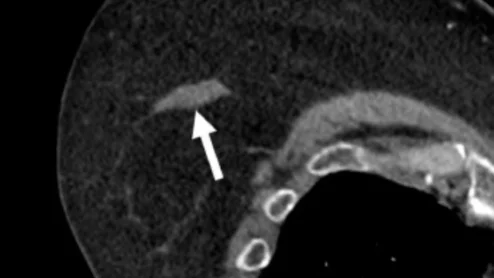

cvi42 | Plaque Circle Cardiovascular Imaging

The use of AI to evaluate plaque buildup in CCTA images has been one of cardiology’s biggest ongoing trends. Implementing this software into existing workflows, however, can be a challenge. An upcoming webinar is focused on providing guidance to hospitals and cardiology practices hoping to learn more about this topic.